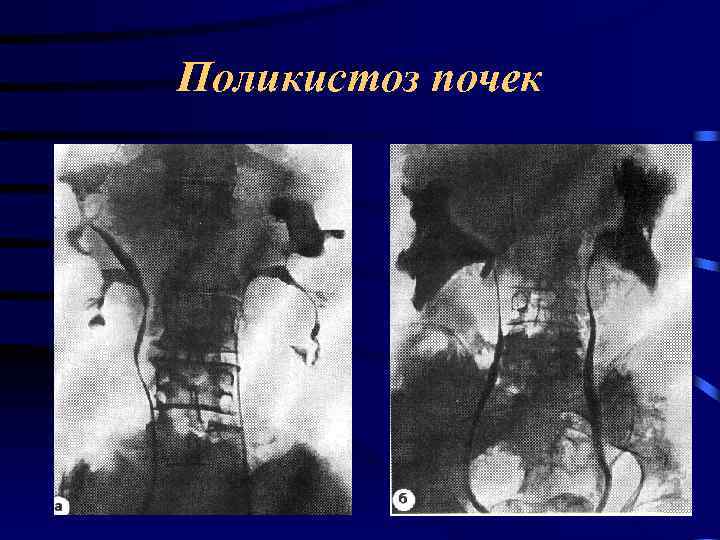

Поликистоз почек

Поликистоз почек

Поликистоз почек

Поликистоз почек

Поликистоз почек

Поликистоз почек